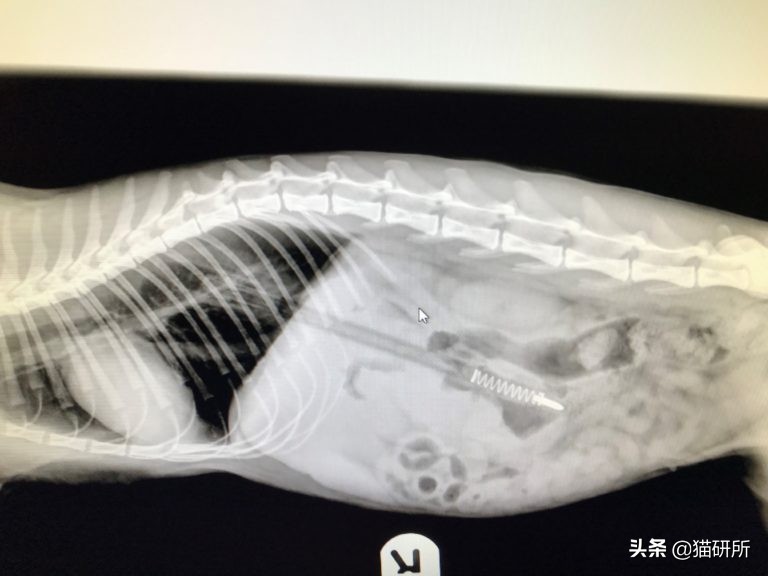

这只1岁半大的猫咪被主人发现时,正躺在落地灯旁的地板上,不停流涎、大便*禁失**,旁边的电线有被啃咬的痕迹。经检查发现猫咪舌头有烧灼的痕迹,X光显示食道、胃、近端小肠处有线状物。手术后,猫咪恢复了健康。

图自:iheartcats